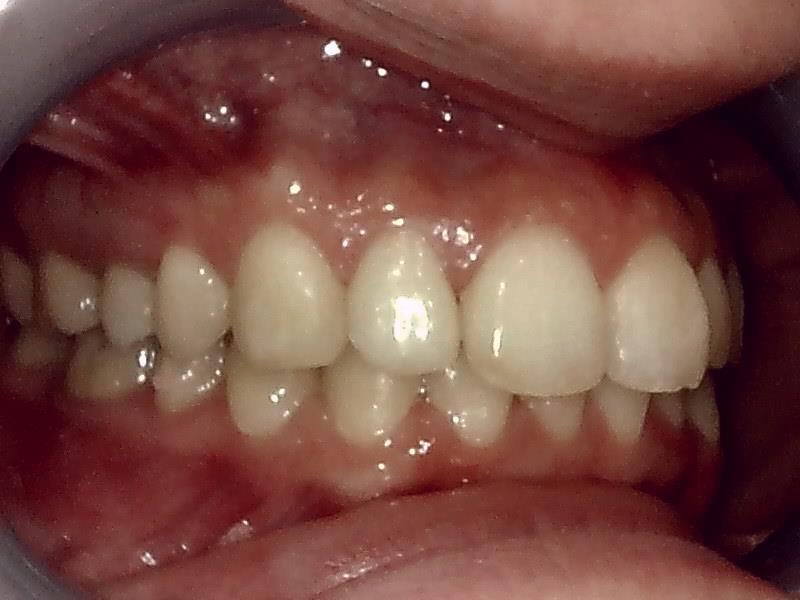

右側